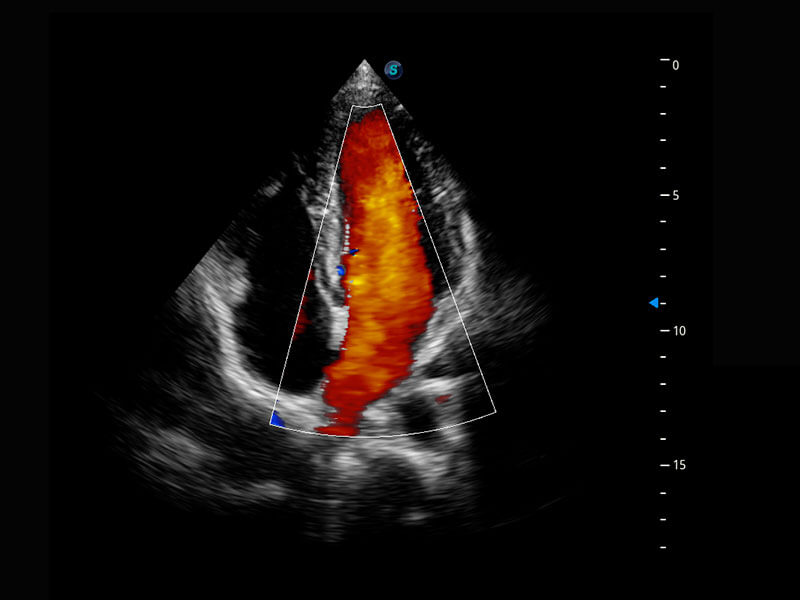

中晚孕筛查

P60提供简单易学易用的高端诊断工具,为您中晚孕筛查提供快速清晰的解剖信息。

乳腺超声 / 新生儿

P60搭载宽频带线阵探头、宽景成像、弹性成像技术,为您提供乳腺应用方案。P60支持高频相控阵探头、线阵探头、腹部高频探头、腹部微凸探头等,丰富的探头群搭载敏感的彩色血流成像,适用于新生儿多种脏器检测要求,满足新生儿筛查需求。

• 新生儿心脏